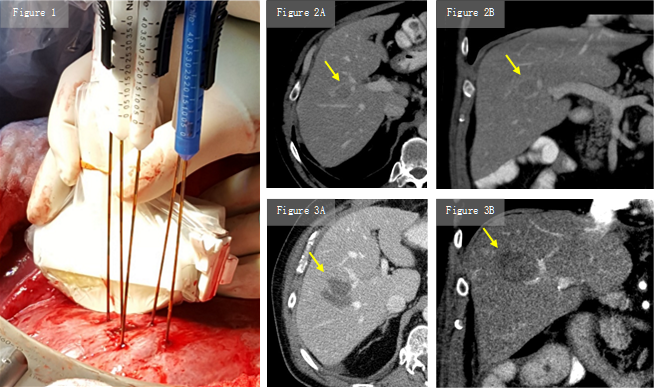

Durch schnelle elektrische Impulse werden die Zellmembranen der Krebszellen geöffnet und durch die Hochspannung der Zelltod der Krebszellen bewirkt.

Die irreversible Elektroporation (IRE) kommt bei der Behandlung von Lebertumoren (max. Größe 6 cm) dann zum Einsatz, wenn klassische Therapieoptionen (chirurgische Resektion) nicht angewendet werden können.

Vor allem bei Tumoren in der Nähe von Gefäßen kann eine Wirkung nachgewiesen werden. Die thermische Ablation von diesen Tumoren würde zu erhöhten Komplikationen bei unzureichender Tumordestruktion (Kühleffekt) führen.

Während der IRE können Blutgefässe und Gallengänge besser geschont werden.